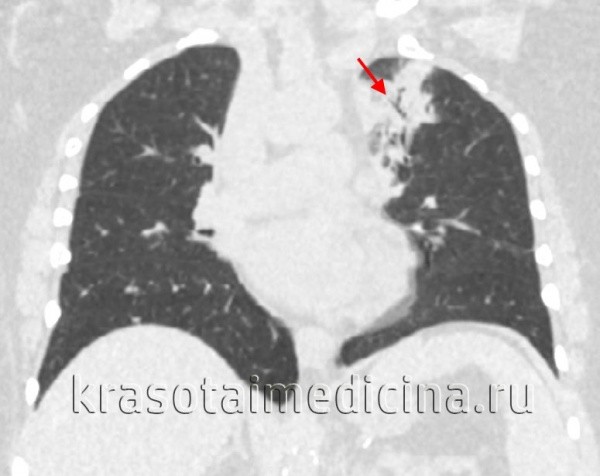

Рентгеногрфия грудной клетки в двух проекциях (прямой и боковой). При пневмониях видны очаговые затемнения, либо долевые.

При необходимости проводится компьютерная или магнитно-резонансная томография легких.

- Рентгенографию органов грудной клетки — выявляет скопление вредных элементов в задних или верхних сегментах нижней доли или заднем сегменте верхней доли, при абсцессе показывает полости.

- Компьютерную томографию органов грудной клетки, как правило, без контрастирования — при подозрении на осложнённое течение пневмонии. С контрастированием — показывает очаги скопления газа или жидкости.

- Рентгенография легких.Рентгенограммы при пневмонии обычно делают в начале заболевания и спустя 3-4 недели для контроля разрешения воспаления и исключения другой патологии (чаще бронхогенного рака легких). При любых видах пневмоний чаще процесс захватывает нижние доли легкого. На рентгенограммах при пневмонии могут выявляться следующие изменения: паренхиматозные (очаговые или диффузные затемнения различной локализации и протяженности); интерстициальные (легочный рисунок усилен за счет периваскулярной и перибронхиальной инфильтрации).